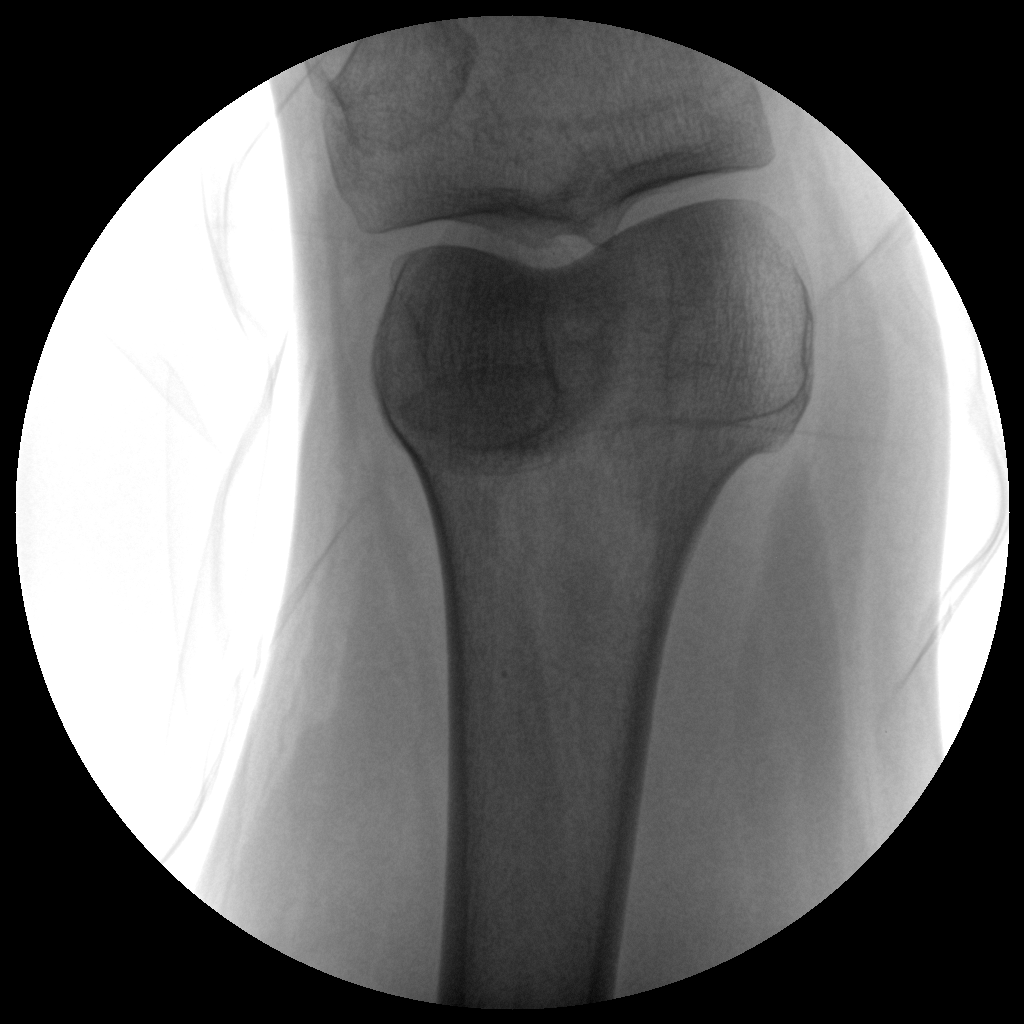

●經(jīng)典影像工作站,可隔室操作避免輻射

●全數(shù)字化百萬(wàn)像素影像系統(tǒng),圖像清晰

●靈活的C臂機(jī)架設(shè)計(jì),滿足臨床大范圍運(yùn)動(dòng)

●臨床功能豐富,具備脈沖控制、數(shù)字?jǐn)z影、自動(dòng)透視等

●具備手持控制器,遠(yuǎn)離主機(jī)也可自由控制